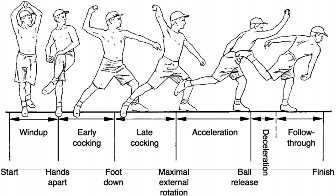

Many studies have been conducted to investigate SLAP tears in the context of overhead throwing. It appears that SLAP tears are most likely to occur during the

late cocking and deceleration phases of throwing due to the increased stress and strain at the superior glenoid/biceps tendon interface and decreased strength of the biceps tendon in these positions. In addition, posterior capsule contracture with consequential increased external rotation and decreased internal rotation of shoulders of overhead throwing athletes can lead to a peel-back phenomenon of the biceps anchor and internal impingement of the rotator cuff between the humerus and the posterosuperior labrum in the late cocking phase, leading to SLAP tears. This is especially true in patients who have over 25 to 30 degrees less internal rotation as compared to the contralateral shoulder.